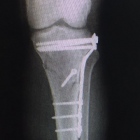

Hola, es pertinente una adecuada valoracion preoperatoria para determinar el riesgo quirúrgico así como una correcta planeacion para determinar la Protesis adecuada a su padecimiento, es conveniente que... Ver más